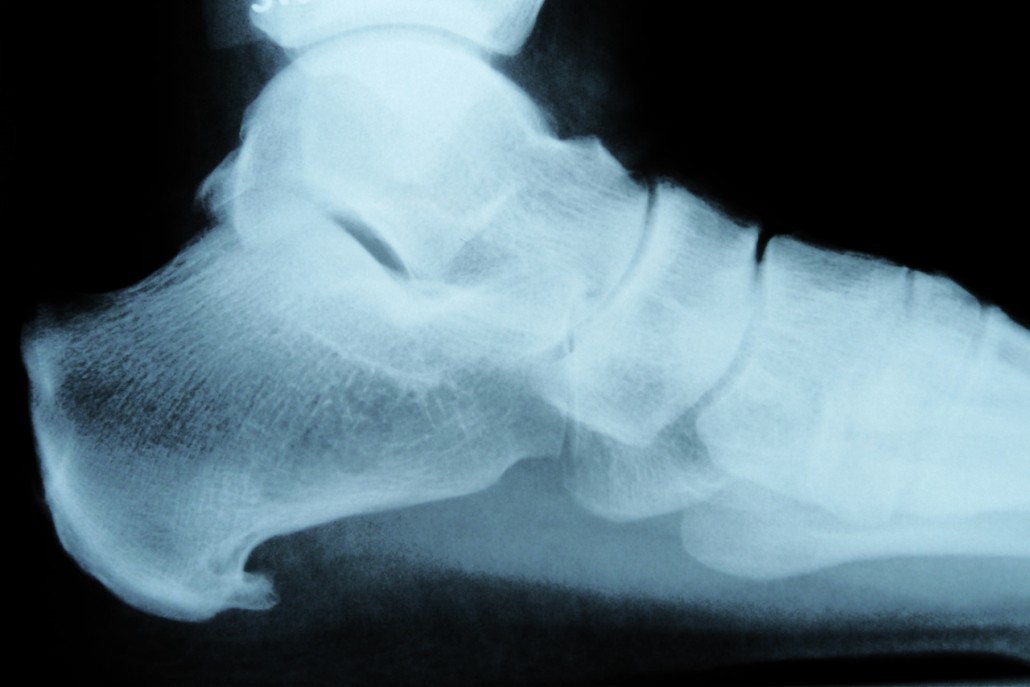

Een hielspoor is een klein aangroeisel aan de voor- en onderzijde van de hiel. Het ontstaat door jarenlang staan, lopen en springen. De platte peesplaat onder de voet ook wel de ‘fascia plantaris’ genoemd trekt jarenlang aan de hiel, waardoor de hiel soms de neiging heeft om extra bot aan te maken. Hierdoor ontstaat een soort aangroeisel de zogenaamde ‘hielspoor’. Deze is goed zichtbaar op een röntgenfoto.